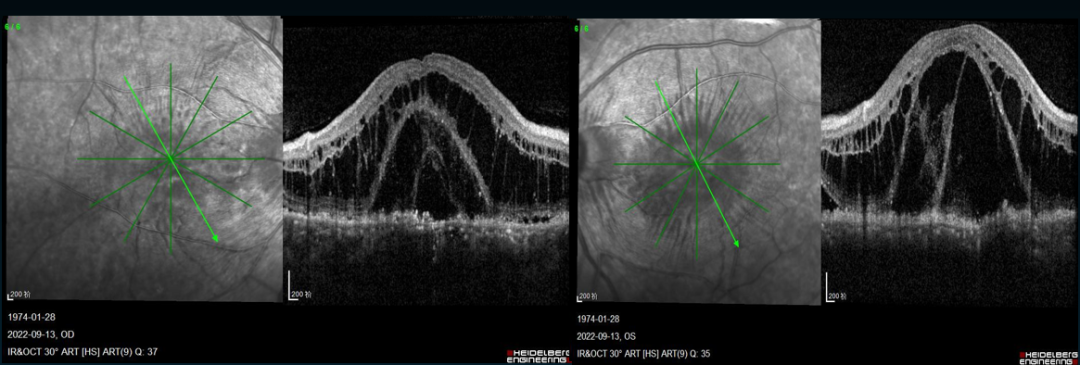

一名48岁的男性,以“双眼视物模糊半年,加重2个月”为主诉就诊,自述近两年出现畏寒、四肢末梢麻木感伴皮肤花斑的情况。眼部体查可见其双眼最佳矫正视力为0.1,双眼前节均透明,无特殊改变。其眼底照相可见黄斑皱褶、水肿。近红外照相可见Elschnig斑。OCT也可以看到明显的黄斑水肿,FFA+ICGA未见血管渗漏,但黄斑区斑驳状窗样缺损,脉络膜黄斑区斑片状低荧光。

就诊时双眼黄斑OCT

患者2月前首诊眼科时,黄斑水肿及斑片状改变未及此次就诊时严重。当时其实验室检查有多项免疫相关指标阳性:自身抗体ANA 1:80\1:160\1:320阳性、抗ds-DNA抗体阳性、类风湿因子IgM阳性、血清铁蛋白含量916.48 ng/ml (21.8-274.66)、血沉37mm/h, 超敏CRP 3.46mg/l,24小时尿蛋白311.6mg/天、尿沉渣RBC 20000个/ml,并且其心脏彩超提示其有心包积液以及右侧胸腔有中量的积液。综上考虑自身免疫性疾病可能性较大,故将患者由眼科转入风湿免疫科,后确诊红斑狼疮、混合结缔组织病,给予糖皮质激素冲击、CTX、MTX以及眼部球周注射糖皮质激素治疗。随着病情进展,患者后部斑片状病灶越来越显著,范围扩大。综上考虑患者为双眼脉络膜缺血、黄斑水肿以及SLE。